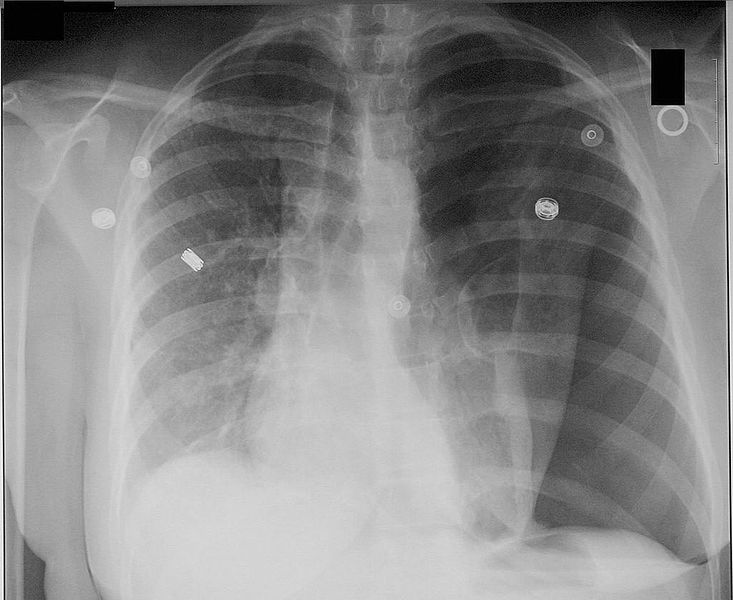

The patient did have a left pneumothorax! The doctor has repositioned the chest tube , and now sats are up to 93%.

(Dimov, 2006; retrieved from Wikipedia, used under Creative Commons license)

Do you see three indications of the pneumothorax?

the edge of his left lung is pushed medially